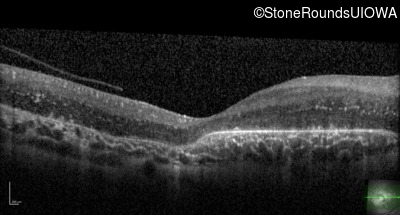

Optical Coherence Tomography - Right - 20/80

Exemplar / OCT Stack